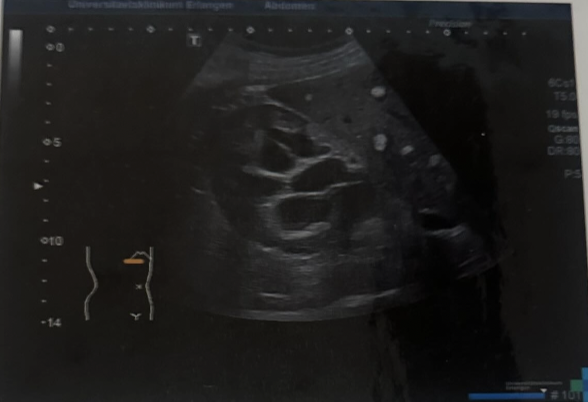

Path?

Severe Hydronephrosis